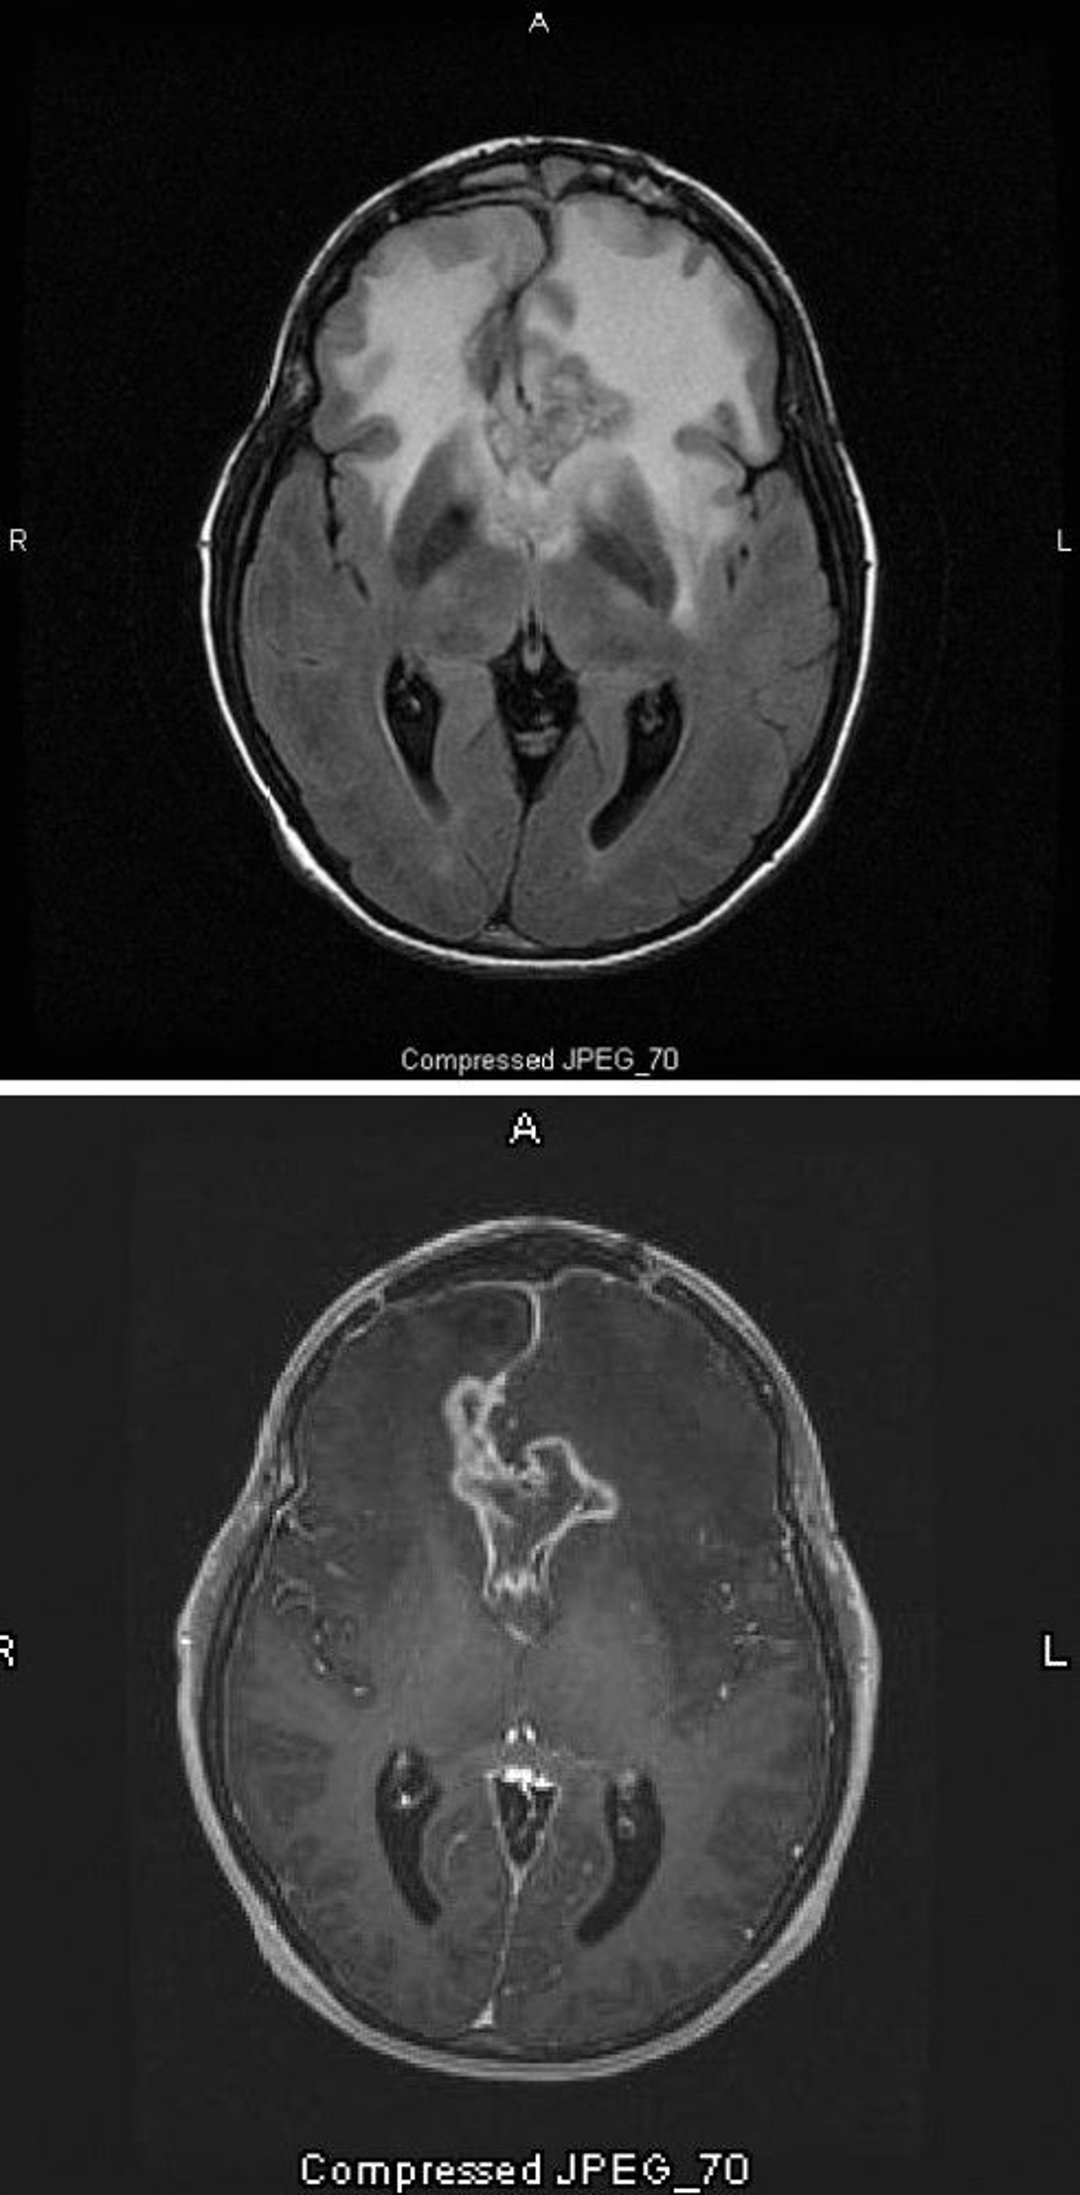

Glioblastoma

The T2-FLAIR MRI scan (top) shows a large, bilateral white (hyperdensity) signal around a glioblastoma, which is the highest grade and most malignant astrocytoma. This particular glioblastoma is called a butterfly glioma because the white signal around the tumor forms the wings of the butterfly; it is caused by cerebral edema. On the T1-weighted scan (bottom), contrast outlines the edge of the tumor (ring enhancement). The edema appears as a darkened area (hypointensity) on T1.

Images courtesy of William R. Shapiro, MD.